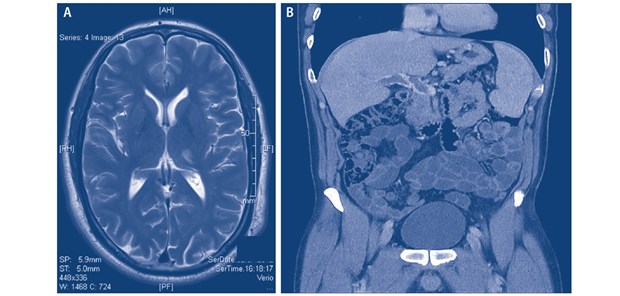

Abb. 3: Thrombophilie bei PNH: Wie hier dargestellt, können Thrombosen an unterschiedlichen Lokalisationen sowohl arteriell als auch venös auftreten: (A) lakunärer Thalamusinfarkt links; (B) Pfortaderthrombose. Beide Ereignisse waren bei dem dargestellten Patienten vor der Erstdiagnose PNH aufgetreten (mit freundlicher Genehmigung von A. Röth, Essen)